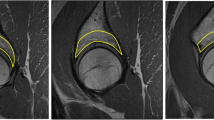

Thirty-five volunteers (30 (SD 11) yrs.) with and without chronic back pain spent 20 min lying in a relaxed unloaded supine position, followed by 20 min loaded in compression, and then 20 min with traction applied. T2-weighted MR images were acquired during the last 5 min of each loading condition. Custom image analysis software was used to segment discs from adjacent tissues semi-automatically and segment each disc into the nucleus, anterior and posterior annulus automatically. A grey-level, co-occurrence matrix with one to four pixels offset in four directions (0°, 45°, 90° and 135°) was then constructed (320 feature/tissue). The Random Forest Algorithm was used to select the most promising classifiers. Linear mixed-effect models and Cohen’s d compared loading conditions.